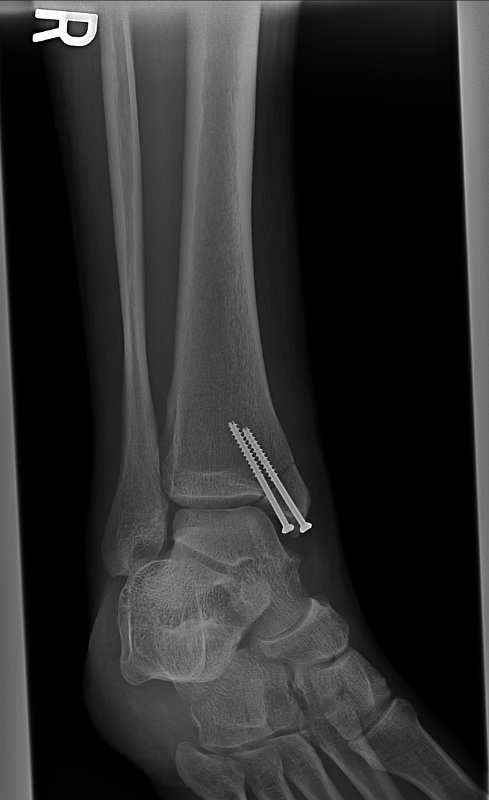

FixedAnkle2